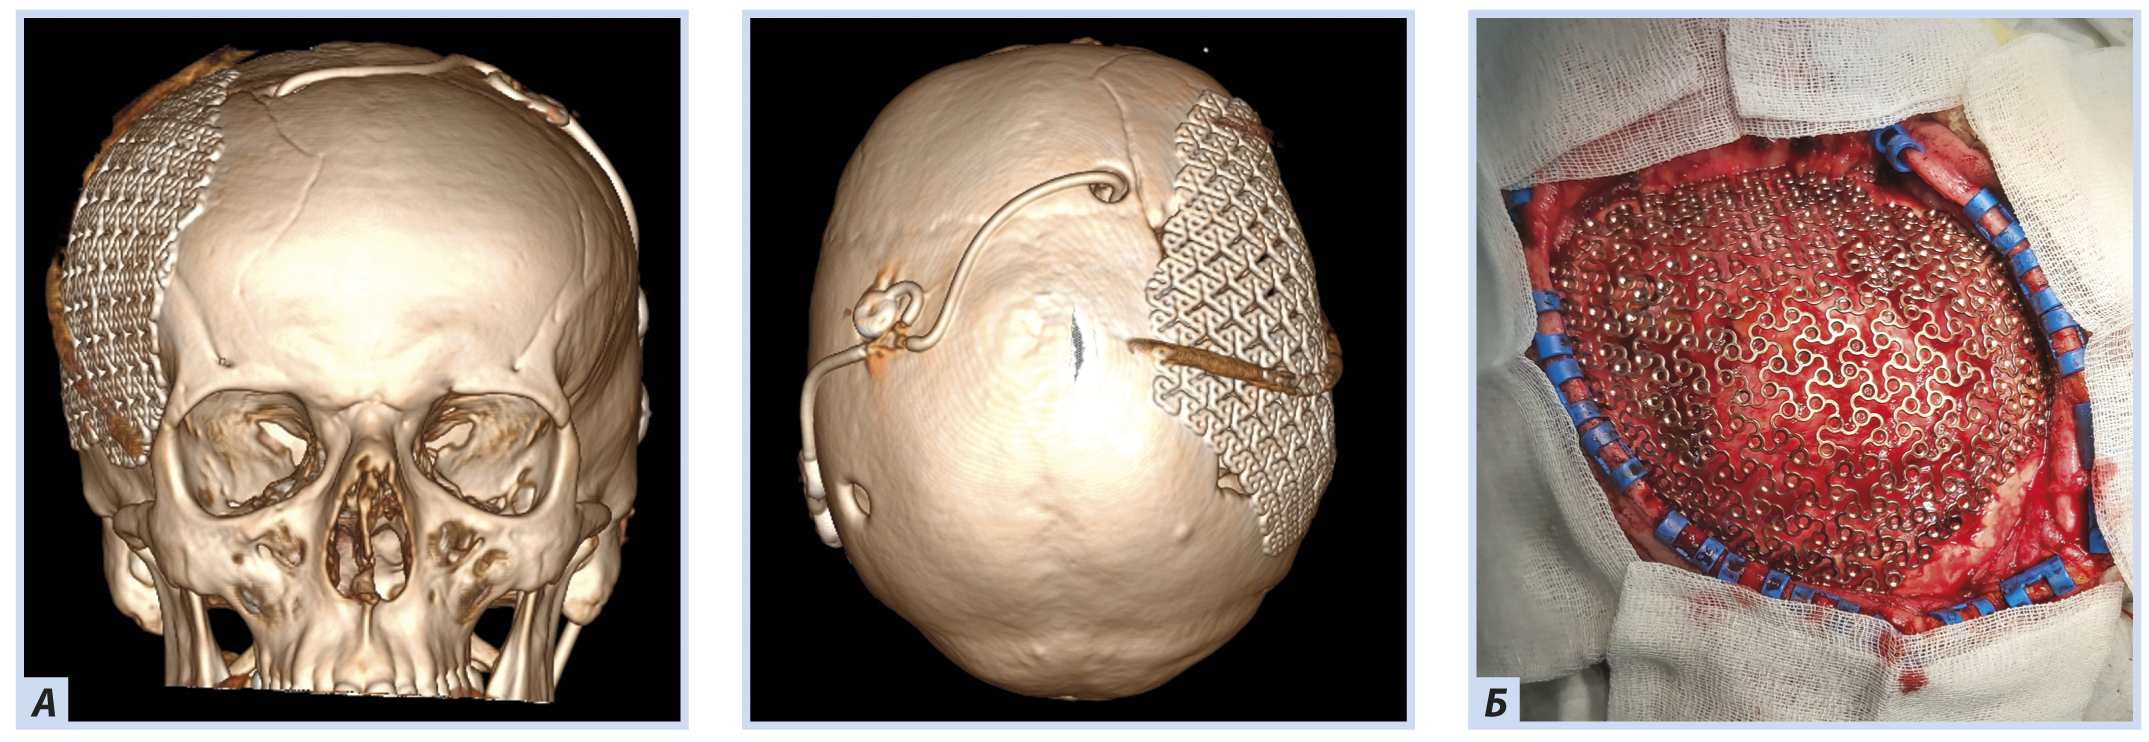

21.04.2020 после предоперационного обследования, регресса воспалительных изменений лабораторных показателей (см. табл. 1–3) и регресса пневмонии по данным КТ пациенту проведена операция в объеме пластики дефекта свода черепа в правой лобно-теменно-височной области титаном с предварительным компьютерным 3D-моделированием (рис. 5).

Рис. 5. Пациент К., 50 лет, с посттравматической гидроцефалией и посттрепанационным дефектом костей свода черепа после операции

Примечание. А — данные 3D-реконструкции компьютерной томограммы головы пациента после операции (на снимках видно удовлетворительное положение титанового имплантата); Б — интраоперационная фотография титанового имплантата, уложенного на дефект костей свода черепа в правой лобно-теменно-височной области.

После операции пациенту выполнена контрольная КТ головы: на снимках отмечены расправление правого бокового желудочка, регресс дислокации срединных структур головного мозга и расправление вещества мозга в области закрытого дефекта костей свода черепа (рис. 6). Давление сброса клапана шунтирующей системы у пациента не менялось и оставалось равным 11 см вод. ст. Также после операции у пациента регрессировали гемодинамические нарушения и икота, связанные с вертикализацией, что позволило продолжить реабилитационные мероприятия.

Рис. 6. Пациент К., 50 лет, с посттравматической гидроцефалией и посттрепанационным дефектом костей свода черепа в правой лобно-теменно-височной области после операции

Примечание. На снимках видны расправление правого бокового желудочка, регресс дислокации срединных структур головного мозга и расправление вещества мозга в области закрытого дефекта костей свода черепа.